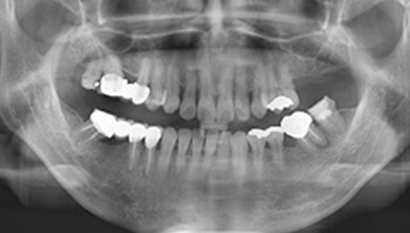

W Dental Clinic Before & After

治療前後の写真

Before

After